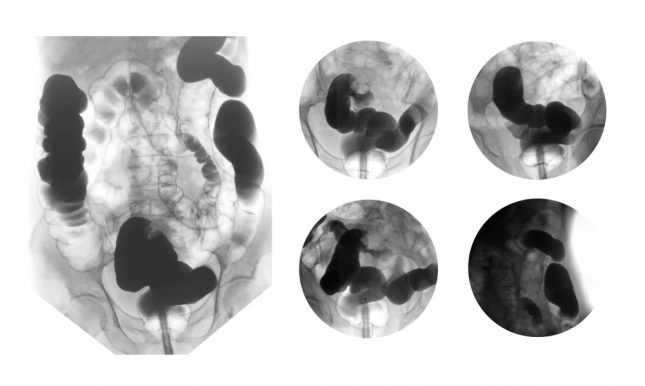

הקבוצה הסעודית מדווחת על מטופלת בת 54, שהתייצגה עם גרורות של סרטן הקיבה בתוספתן שנמצאו באופן מקרי בניתוחה השני שבו עברה כריתה של המעי עקב לכידת מעי בבקע פנימי – סיבוך של ניתוח סרטן הקיבה העיקרי שעברה קודם לכן.

בדו"ח שפורסם נסקרים שישה דיווחים על גרורות סרטן קיבה לתוספתן. הגרורות היו סימפטומטיות בארבעה מקרים ומבודדות (ללא גרורות באתרים נוספים) בשלושה מקרים. האבחנה עוכבה בארבעה מקרים כיוון שלא היו עדויות לגרורות באבחון הגידול הראשוני; אפנדקטומי בוצעה בכל המקרים. הפרוגנוזה של המקרים היתה שונה במידה ניכרת.